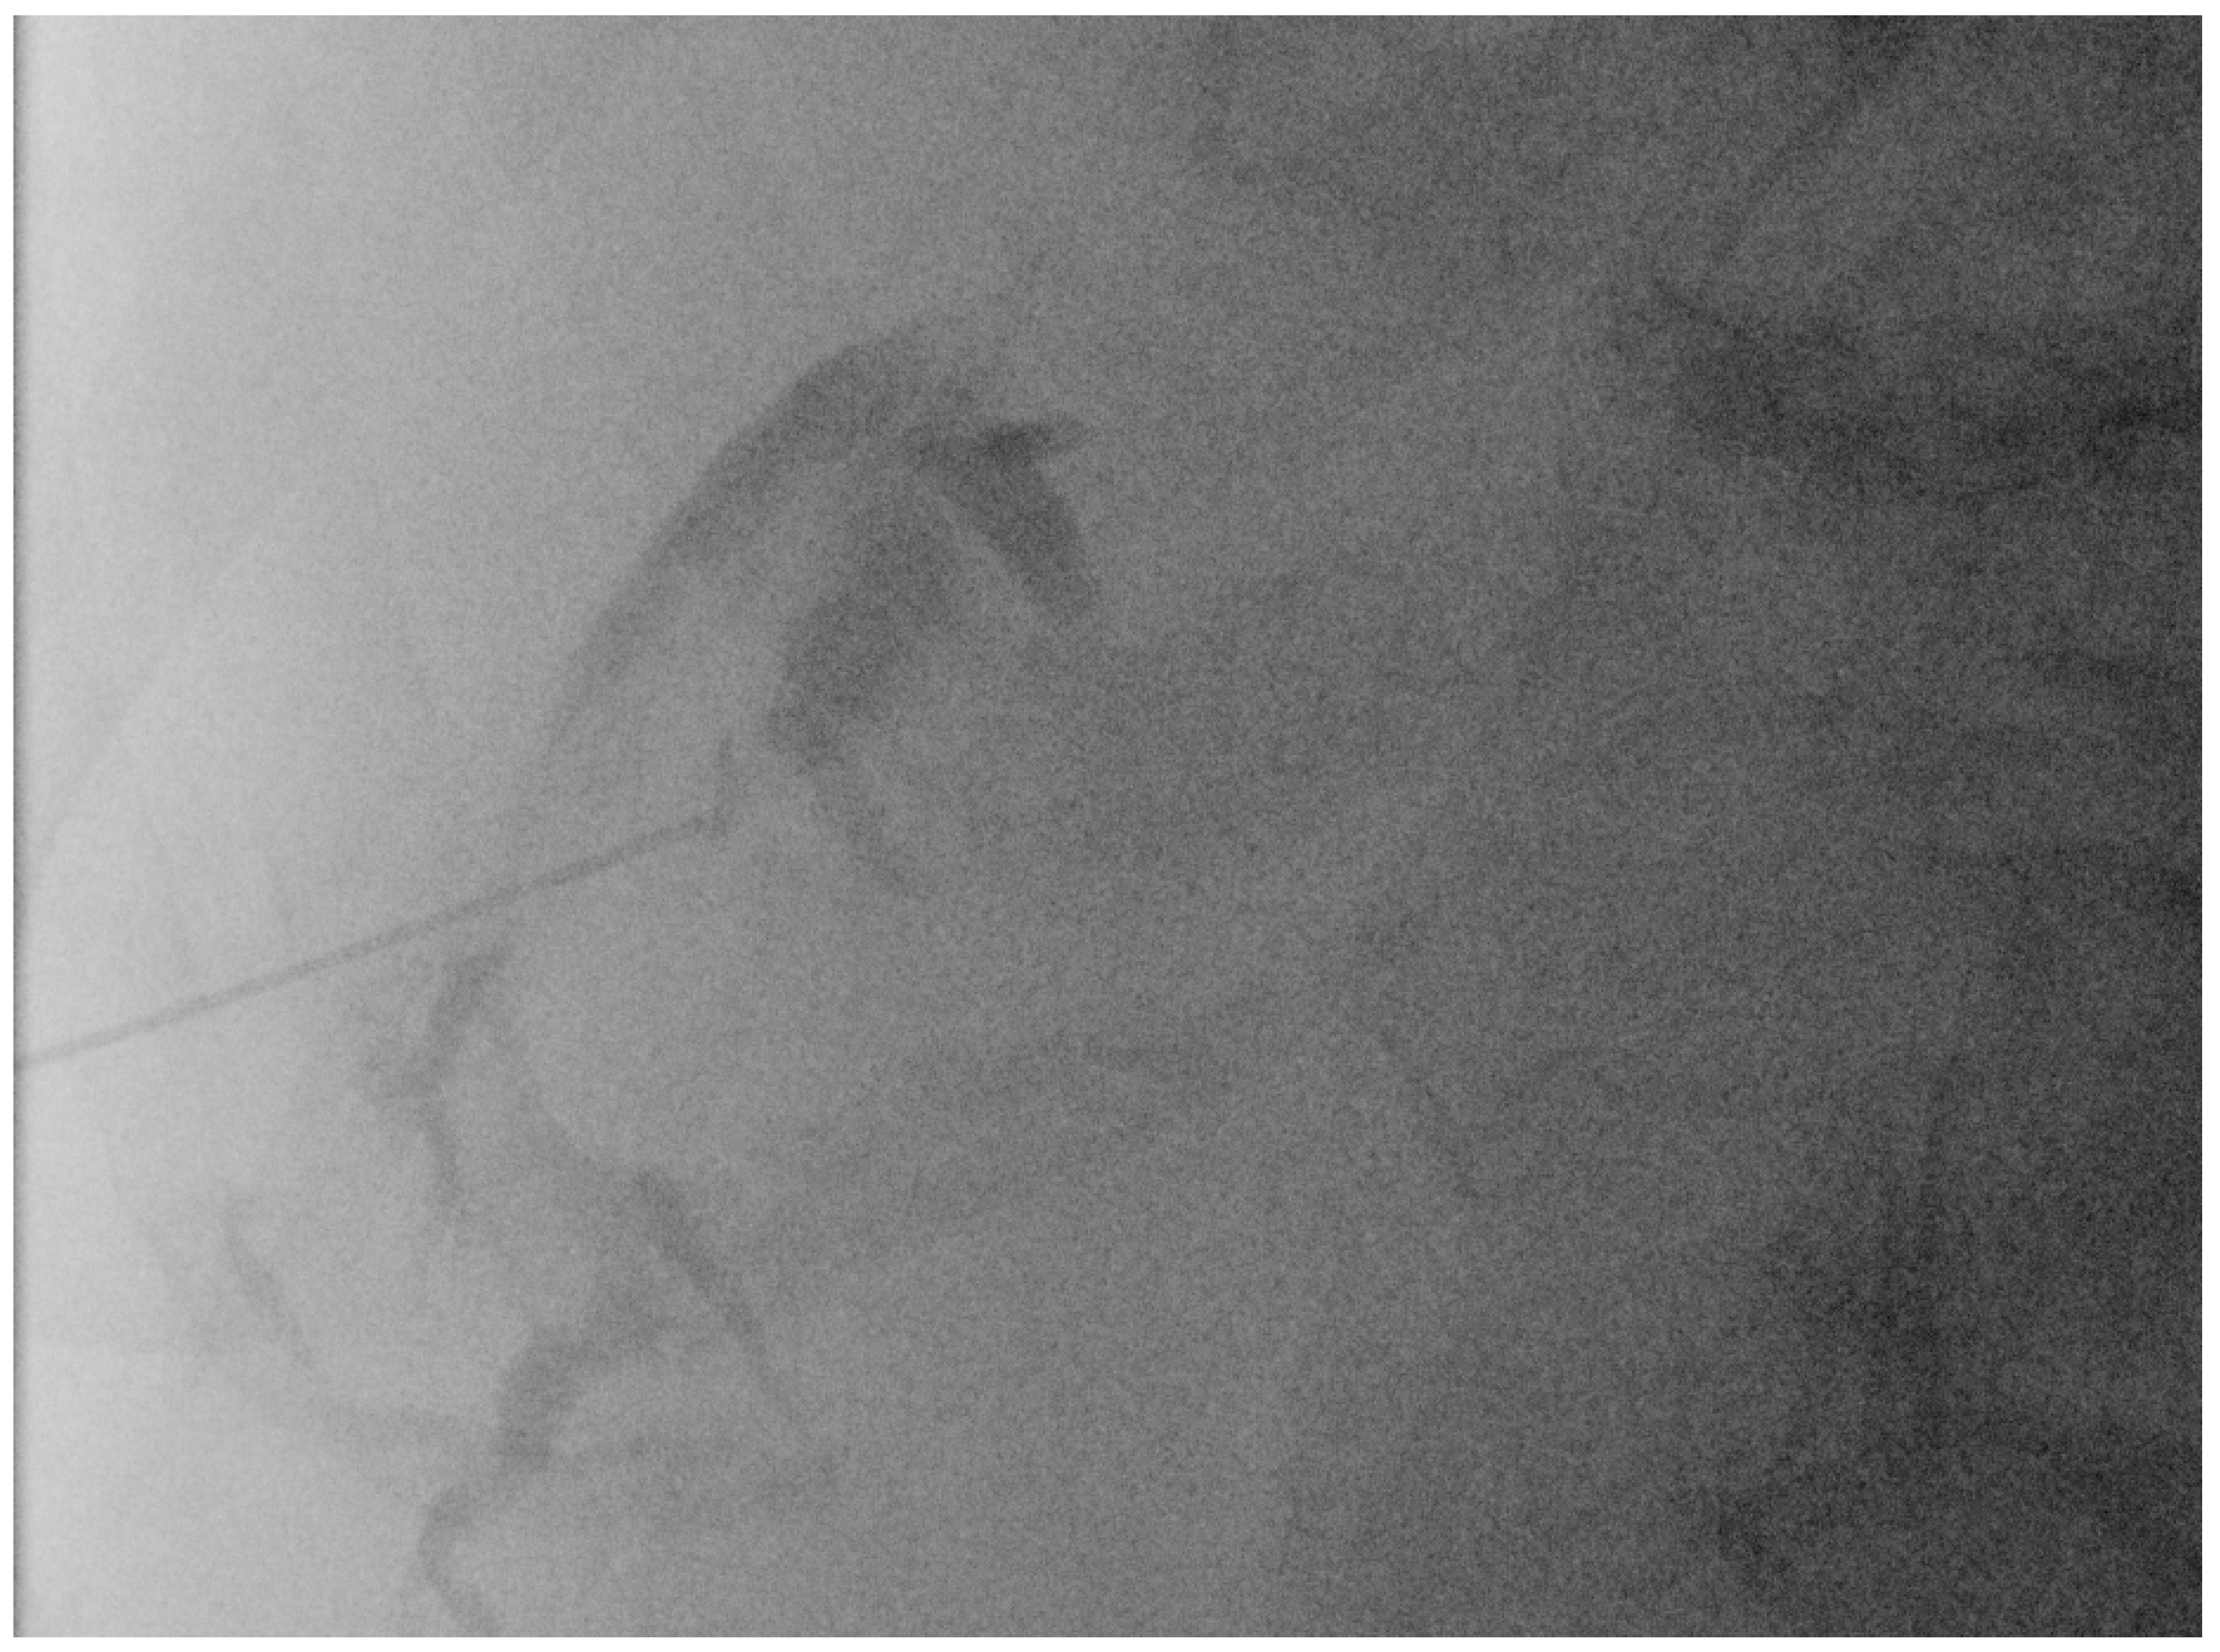

Again, the “in plane” approach is recommended to depict the needle in real time and continuously on its way. This is mandatory because iatrogenic perforation of the posterior gallbladder wall must be avoided. Both the drainage techniques, Seldinger (Figure 11a–c) and trocar (direct puncture, cf. Figure 10), may be used, depending on the physician’s preferences [43,58].

Figure 11.

When using the Seldinger technique, first a Chiba needle is placed in the gallbladder (a), through which a 0.035” guide wire with bended tip is inserted (b). Plastic pigtail drainage (c) is then advanced over the guide wire.

We recommend the use of 8F or 10F pigtail drainage. If it is inserted using Seldinger’s technique, dilatation is not necessary. If the guide wire is confirmed to be in the correct place and is secured well, drainage placement can be performed without US visualisation [43,76].